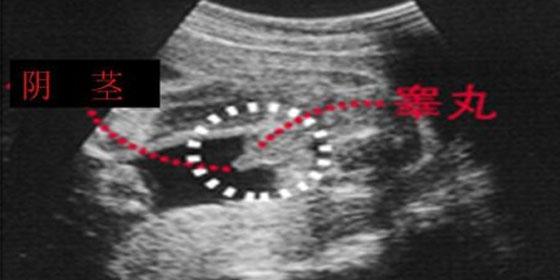

男宝宝四维彩超图

"凸出的工具" 是他的标识表记标帜: 你们看到圆圆的是蛋蛋,若是看到圆圆的加小肠的就是全数JJ